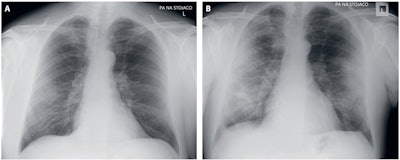

Rorat and colleagues investigated the usefulness of a simple chest x-ray scoring scale to assess the presence and severity of inflammation in the course of COVID-19. They also evaluated the possibility of nonradiologist physicians interpreting the presence and degree of inflammation in the lungs on their own. The study consisted of a retrospective analysis of chest x-ray records and images of 152 consecutive patients between 19 and 96 years old who were hospitalized with SARS-CoV-2 infection between March and April 2020.

In 77 of 152 cases, the chest x-ray revealed inflammation features, with bilateral abnormalities found in the majority (62.3%) of cases. Lower lung lobes were involved more often than the upper ones, and the left lobe more often than the right one, the researchers found.